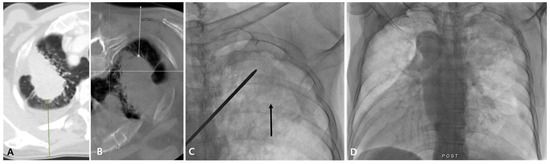

Figure 1.

Diagnostic failure of fluoroscopy-guided PTNB with the aid of planning CBCT for a lung nodule in a 78-year-old man with lung adenocarcinoma. A diagnostic CT image (A) and planning CBCT image (B) show a 28 mm nodule (white arrow) in the left upper lobe with a long lesion depth (85 mm, bold white dashed line). On fluoroscopy, the nodule is identifiable (black arrow) (C) and no immediate PTNB-related complications occurred (D). The pathologic specimen length of the lesion was 1 mm, and the pathology result was non-evaluable in this case.